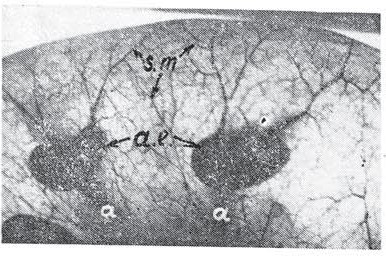

. На рис. 1 изображена бесконтрастная трансиллюминационная ангиограмма участка передней стенки поперечной ободочной кишки, расположенного между двумя отрезками прямых внутристеночных артерий и вен. От этих артерий по направлению к указанному сегменту отходят косопоперечно ветви, анастомозирующие со смежными ветвями того же сосуда, а также с ветйями, связанными с противолежащим сосудом. Возникает довольно густая подслизистая сеть. На приведенной ангиограмме определяются наслаивающиеся друг на друга сплетения субсерозного (s.s.), подслизистого (s.m.) слоев. Местами видны сосуды слизистой ,(т.). В формировании описываемой сосудистой сети подслизистого слоя помимо двух смежных прямых сосудов участвует и крупная ветвь (А), отходящая от прямой внутристеночной артерии и разделяющая этот промежуток на две части. Субсерозное сплетение также формируется ветвями интрамуральных прямых артерий. На бесконтрастной трансиллюминационной ангиограмме сигмовидной ободочной кишки (рис. 2) контурируются сосуды продольного мышечного слоя (m.s.). Дифференцируются, артерии и вены (a. et v.). Последние дают более интенсивные теневые изображения.

Рис. 1. Бесконтрастная трансиллюминационная ангиограмма отрезка передней стенки поперечной ободочной кишки.